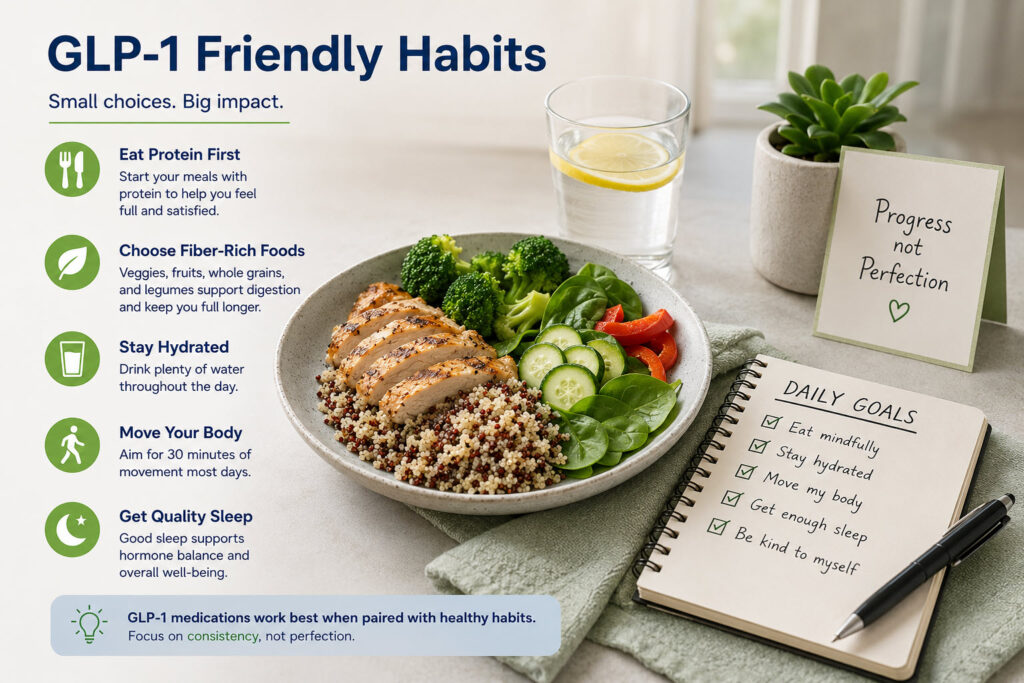

Tuesday, June 16 – People taking popular weight-loss drugs such as Ozempic, Wegovy, Mounjaro, and Zepbound may be losing pounds, but they could also be moving less. Researchers analyzing Fitbit data found that daily step counts and exercise levels dropped after people started these medications, despite successful weight loss. Because the drugs can reduce muscle mass along with fat, the decline in physical activity raises concerns about preserving strength and long-term health.

Study finds exercise decreases among people taking GLP-1 medication

Sunday, June 14 – Adults with obesity who lost weight with glucagon-like peptide-1 (GLP-1) receptor agonist medications significantly decreased their physical activity, which is essential to protect muscle, according to a study presented at ENDO 2026, the Endocrine Society’s annual meeting in Chicago.